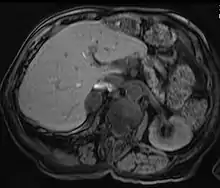

Liver

Hepatic adenomas are a rare benign tumour of the liver, which may present with hepatomegaly or other symptoms.